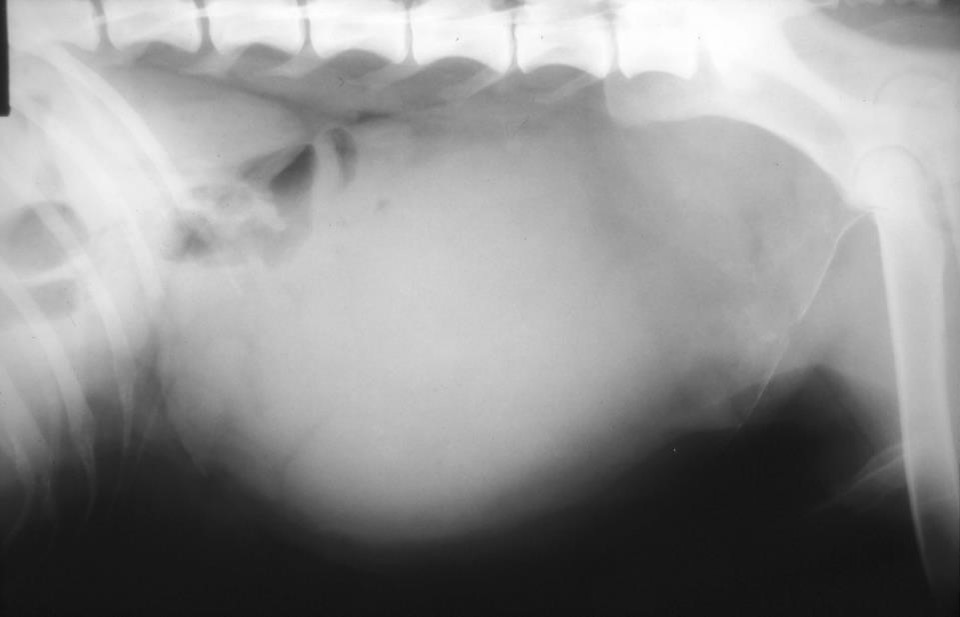

Dog and dysuric

Large mass mid-cd abdomen

What is the most likely diganosis?

Bladder neoplasia

Extra parenchymal prostatic cyst

What has created this image?

What can be seen?

Pneumocystogram

Bladder normal – just displaced

Parenchymal cyst

You can see a mineral line and this is due to cyst cause mineralised lining (immediately puts this top of D/D)